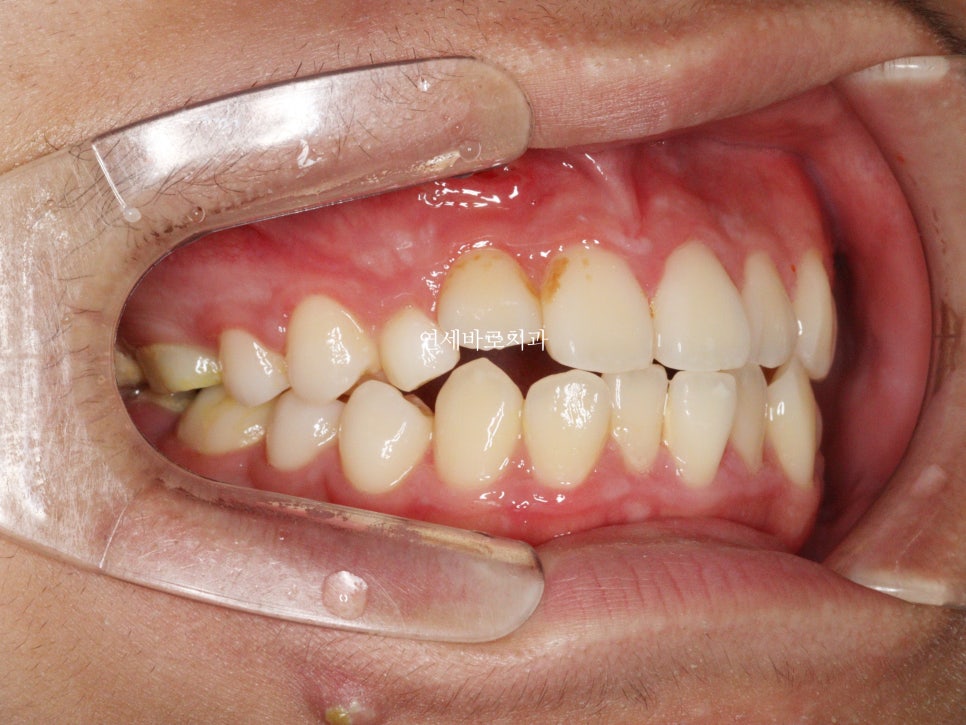

시작 전 모습입니다.

어머니도 아이가 매복치아가 있는지 전혀 모르고 있다가 우연히 교정상담하러 와서 발견한 경우입니다.

그 심미적 문제가 이것입니다.

화면의 왼쪽은 작은 어금니

오른쪽은 송곳니 입니다.

그래서 모양이 다르죠.

이런문제가 있긴 하지만 거의 티가 나진 않습니다.